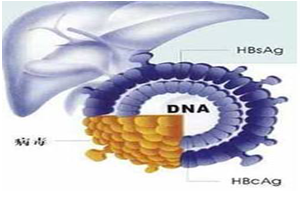

科学对待乙肝 不必盲目恐慌

科学对待乙肝 不必盲目恐慌

专家解释,不同的感染情况传染性是不同的,而且乙肝主要是通过体液传染,并不像大家想的那样,一起吃饭、面对面说话就会传染,所以不必谈“乙肝”色变,对周围携带乙肝病毒的人“敬而远之”。

专家解释,不同的感染情况传染性是不同的,而且乙肝主要是通过体液传染,并不像大家想的那样,一起吃饭、面对面说话就会传染,所以不必谈“乙肝”色变,对周围携带乙肝病毒的人“敬而远之”。关键字:乙肝病毒,血液指标,转氨酶

科学对待乙肝 不必盲目恐慌

专家解释,不同的感染情况传染性是不同的,而且乙肝主要是通过体液传染,并不像大家想的那样,一起吃饭、面对面说话就会传染,所以不必谈“乙肝”色变,对周围携带乙肝病毒的人“敬而远之”。关键字:乙肝病毒,血液指标,转氨酶 肝脏疾病领域研究进展汇总(第34期)(二)